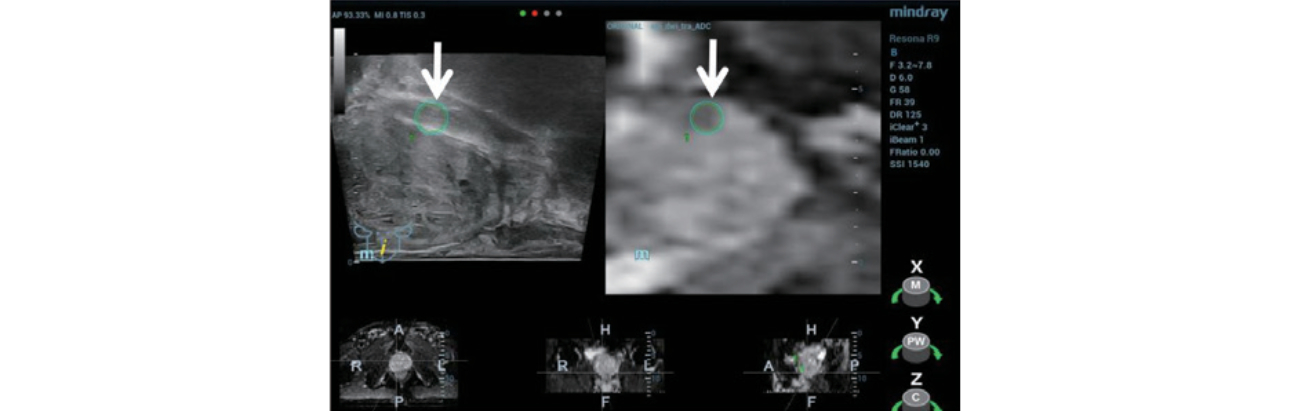

Step 1: 적합한 MRI sequence(Figure 2) 선택 후 Resona 9의 데이터 세트를 실시간 초음파 검사로 import 하였습니다.

trus-mri-fusion-fig2-pc

형상2. 전립선 오른쪽 전엽에 있는 저신호 병변이 ADC(Apparent diffusion coefficient/표관확산계수) MRI sequence에서 가장 명확하게 표시됨.